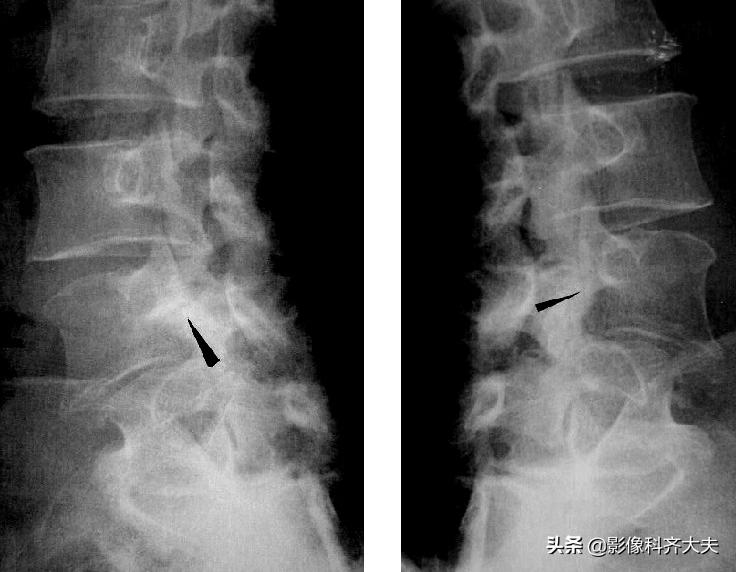

上下关节突间的椎板,称为椎弓峡部,此处骨折常发生在腰4或腰5,因身体重力向前分力作用,可使椎体向前滑脱。椎弓峡部骨折,以脊柱斜位X线片显示清楚。

双斜位显示椎弓峡部骨折线影